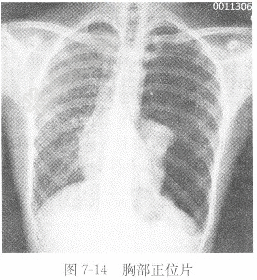

试题详情单项选择题女性,25岁,胸闷,呼吸困难半小时,X线图像见图7-14,X线诊断为( )。 A、左肺炎B、正常胸片C、左肺结核D、左气胸正确答案:关注下方微信公众号,搜题查看答案热门试题心脏大上、下消化道造影如何根据心电图判断心肌梗死发生的部位?葡萄糖耐量试验癌抗原125(CA125)γ-谷氨酰转移酶(GGT)室性心动过速检查动脉血氧分压(PaO2)心房颤动检查胸腔积液血清氢参考值血清总铁结合力肝癌硬膜外血肿正常胸部位片胃癌心肌梗死出现的ST段抬高应与哪些疾病鉴别颅骨骨折血浆纤维蛋白原(FG)X线片